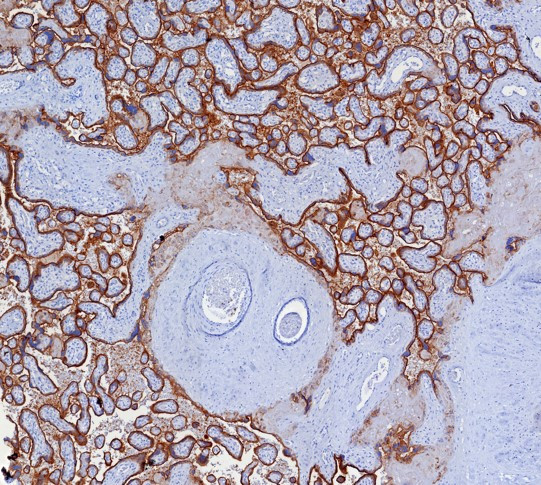

Programmed death receptor ligand 1 (PD-L1, also called B7-H1) is a recently described B7 family member. To date, one specific receptor has been identified that can be ligated by PD-L1. This receptor, programmed death receptor 1 (PD-1), has been shown to negatively regulate T-cell receptor (TCR) signaling. Upon ligating its receptor, PD-L1 has been reported to decrease TCR-mediated proliferation and cytokine production. PD-L1 expression was found to be abundant on many murine and human cancers and could be further up-regulated upon IFN-gamma stimulation. Thus, PD-L1 might play an important role in tumor immune evasion.